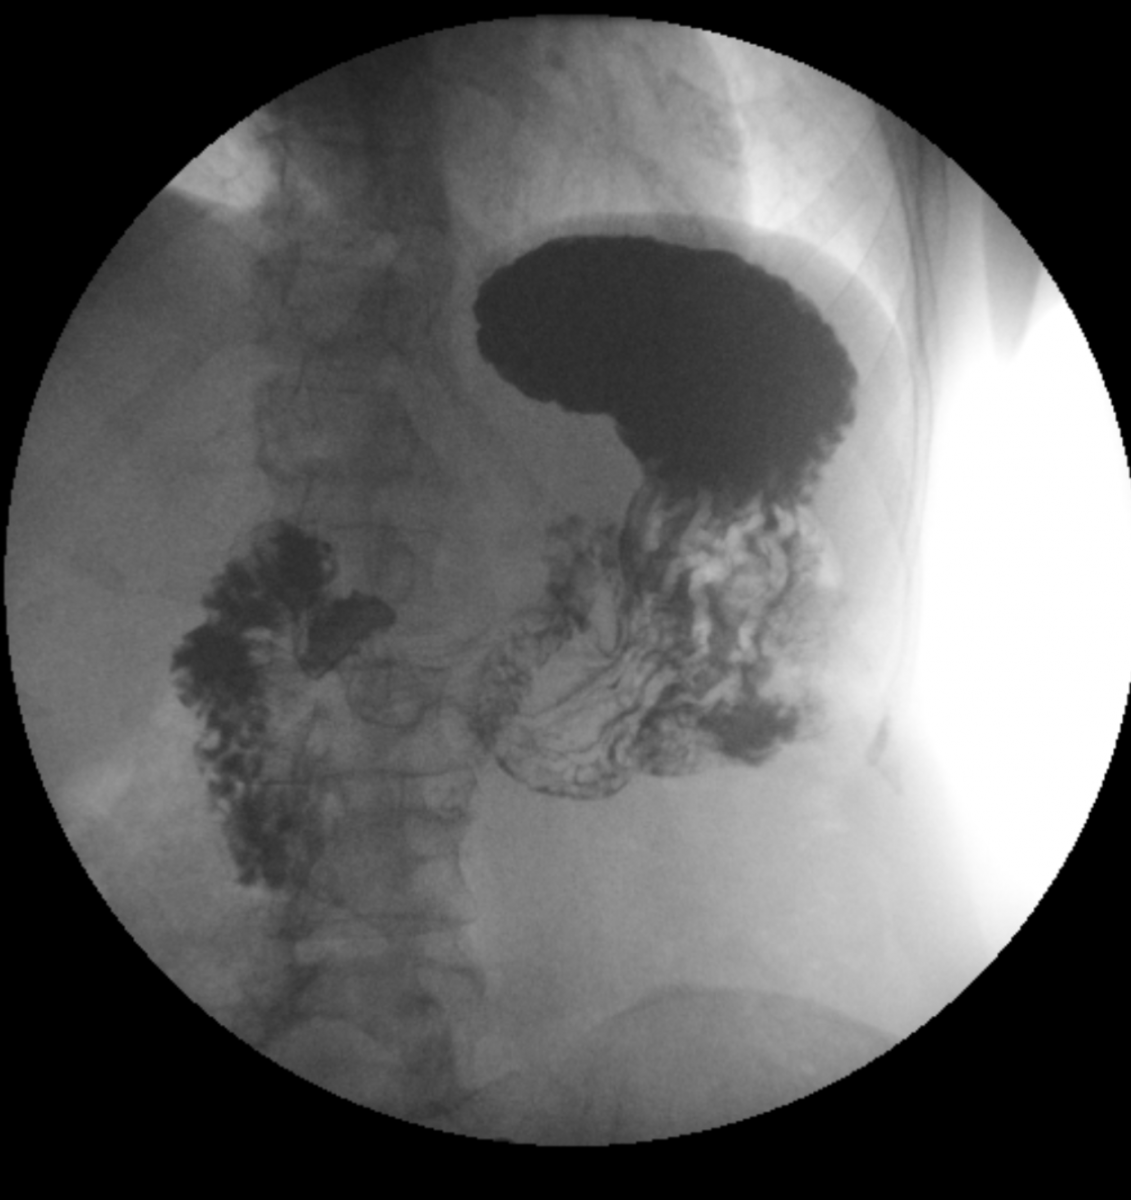

Jedná se o radiologickou vyšetřovací metodu, která pomocí rentgenového záření umožňuje zobrazení lidského těla v reálném čase. Využívá se především k zobrazení trávící trubice (jícnu, žaludku, dvanácterníku, tenkého a tlustého střeva), zobrazení žlučového stromu (ERCP), zobrazení ostatních dutých orgánů – na našem pracovišti zejména močového měchýře a vývodných cest močových, dále některých patologií (píštěle…) apod. Orgány jsou zobrazovány pomocí kontrastní látky, která zabraňuje průchodu rentgenového záření.

Jak je napsáno výše, nejčastější využití skiaskopie je při vyšetření trávicí trubice. Pro její zobrazení je nutné podání kontrastní látky. Nejčastější kontrastní látkou je baryová suspenze, která má různou hustotu, dle vyšetřované oblasti, má bílou barvu a chuť podobnou křídě, ve většině případů pro komfort pacienta doplněnou různými, převážně ovocnými příchutěmi. Při vyšetření se navíc používá plyn pro dosažení tzv. dvojího kontrastu – přímo aplikovaný při vyšetření tlustého střeva.

Vyšetření polykacího aktu, jícnu, žaludku, dvanácterníku a pasáž tenkým střevem

Jedná se o šetrnou metodu sloužící k diagnostice chorobných změn horní části trávicí trubice.

Kontrastní látka se pije ústy, vyšetření se provádí vestoje a vleže, průchod kontrastní látky lékař sleduje na monitoru a zachycuje na snímcích.